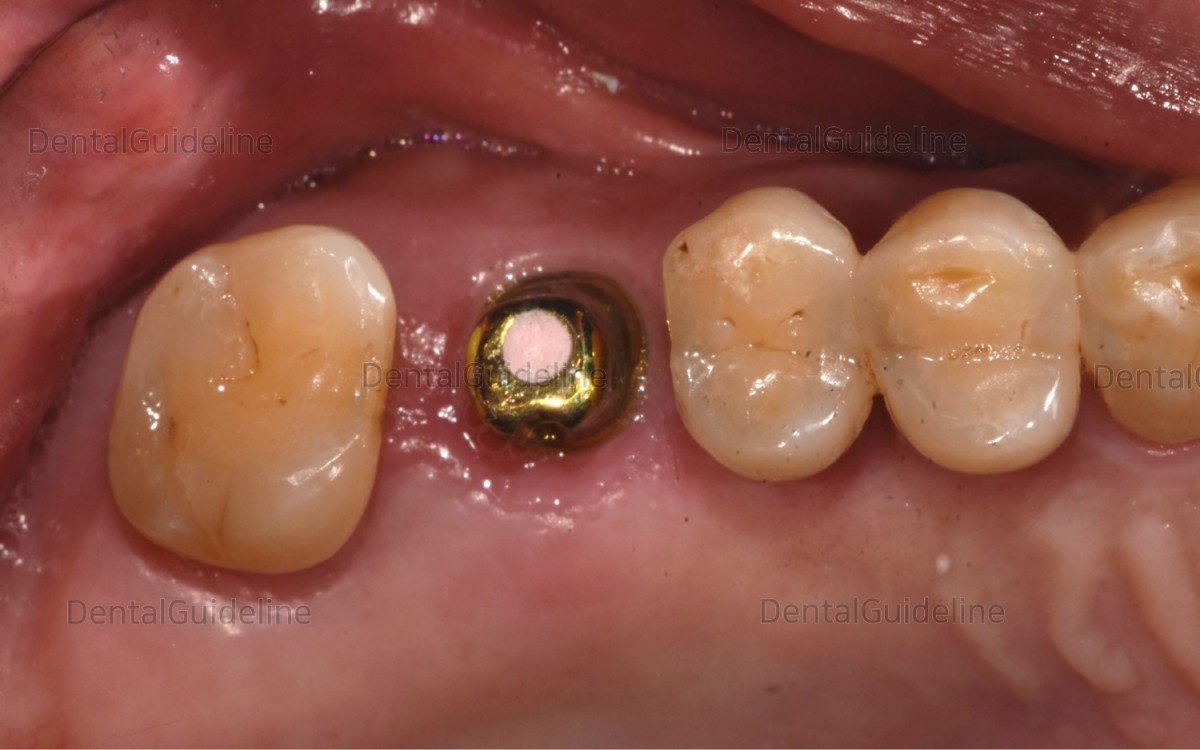

5. 10 weeks after implant placement. On the day of the second surgery.

![]()

6. The fixation was exposed using a tissue-punching instrument.